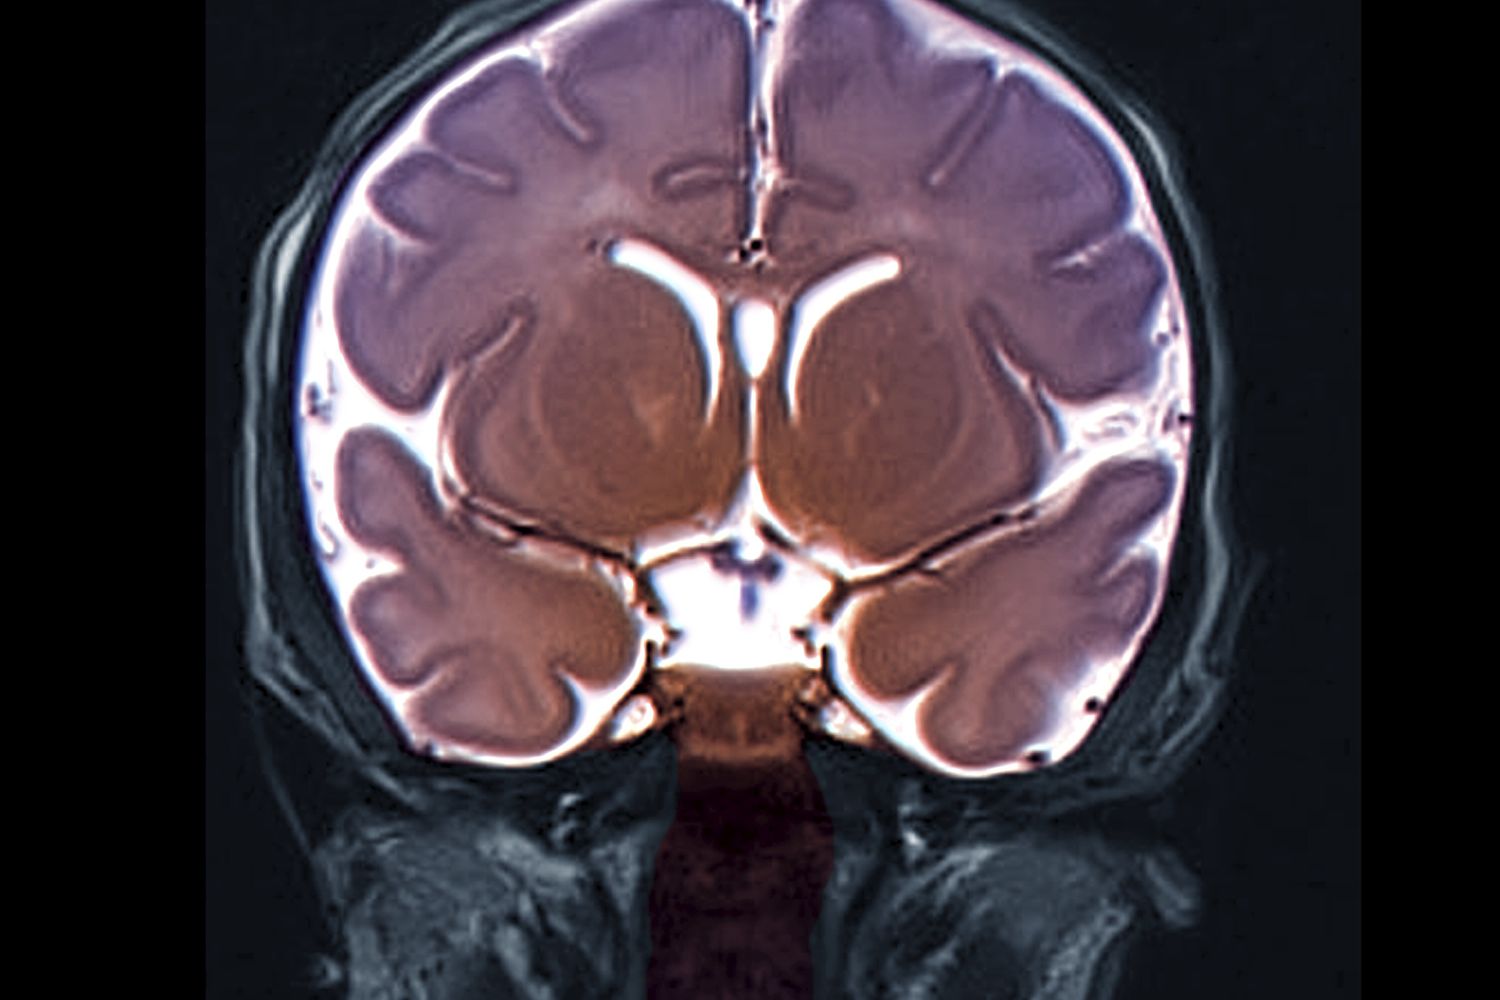

Nel 2022 i suoi sintomi si erano aggravati portandole depressione e perdita di memoria, tanto da richiedere il ricovero all'ospedale di Canberra. Una risonanza magnetica del cervello ha rivelato anomalie che hanno richiesto un intervento chirurgico.